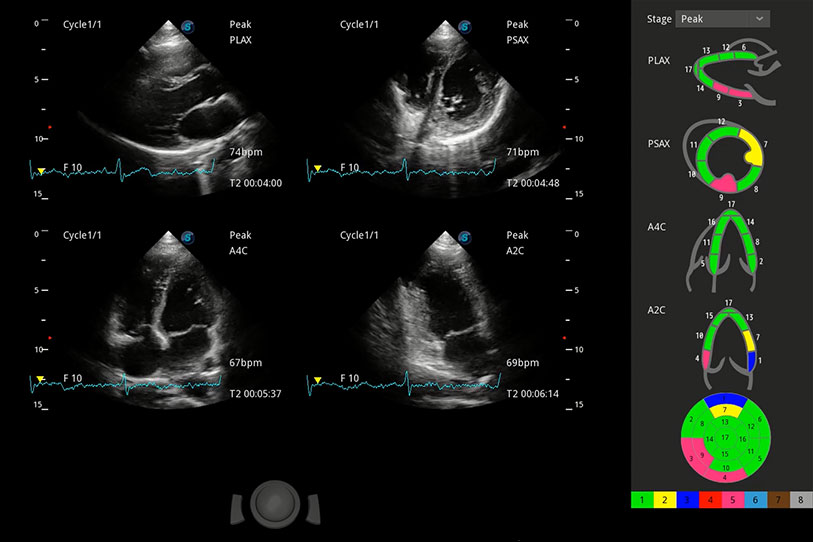

能夠基于左心室壁追蹤和辛普森法,自動(dòng)計(jì)算射血分?jǐn)?shù),支持多個(gè)可移動(dòng)點(diǎn)描跡,與手動(dòng)測量相比,極大節(jié)省了動(dòng)物醫(yī)生的時(shí)間和精力。

具備多種協(xié)議可選,同時(shí)支持17階段劃分法和專業(yè)的SE報(bào)告。

通過360度任意調(diào)節(jié)3條M型取樣線,在同一心動(dòng)周期上觀察心臟不同位置的運(yùn)動(dòng)曲線,得到準(zhǔn)確的心功能測量數(shù)據(jù),有效評估心肌運(yùn)動(dòng)及左心室功能。

實(shí)時(shí)用顏色表示心肌組織運(yùn)動(dòng),觀察和定量組織的運(yùn)動(dòng)情況,對快速檢測與評估心肌的灌注和活性、電傳導(dǎo)及心肌收縮和舒張功能等均能提供重要的診斷信息。

當(dāng)心臟測量結(jié)果超出正常范圍時(shí),可實(shí)時(shí)預(yù)警提示動(dòng)物醫(yī)生,減少疾病漏診概率。